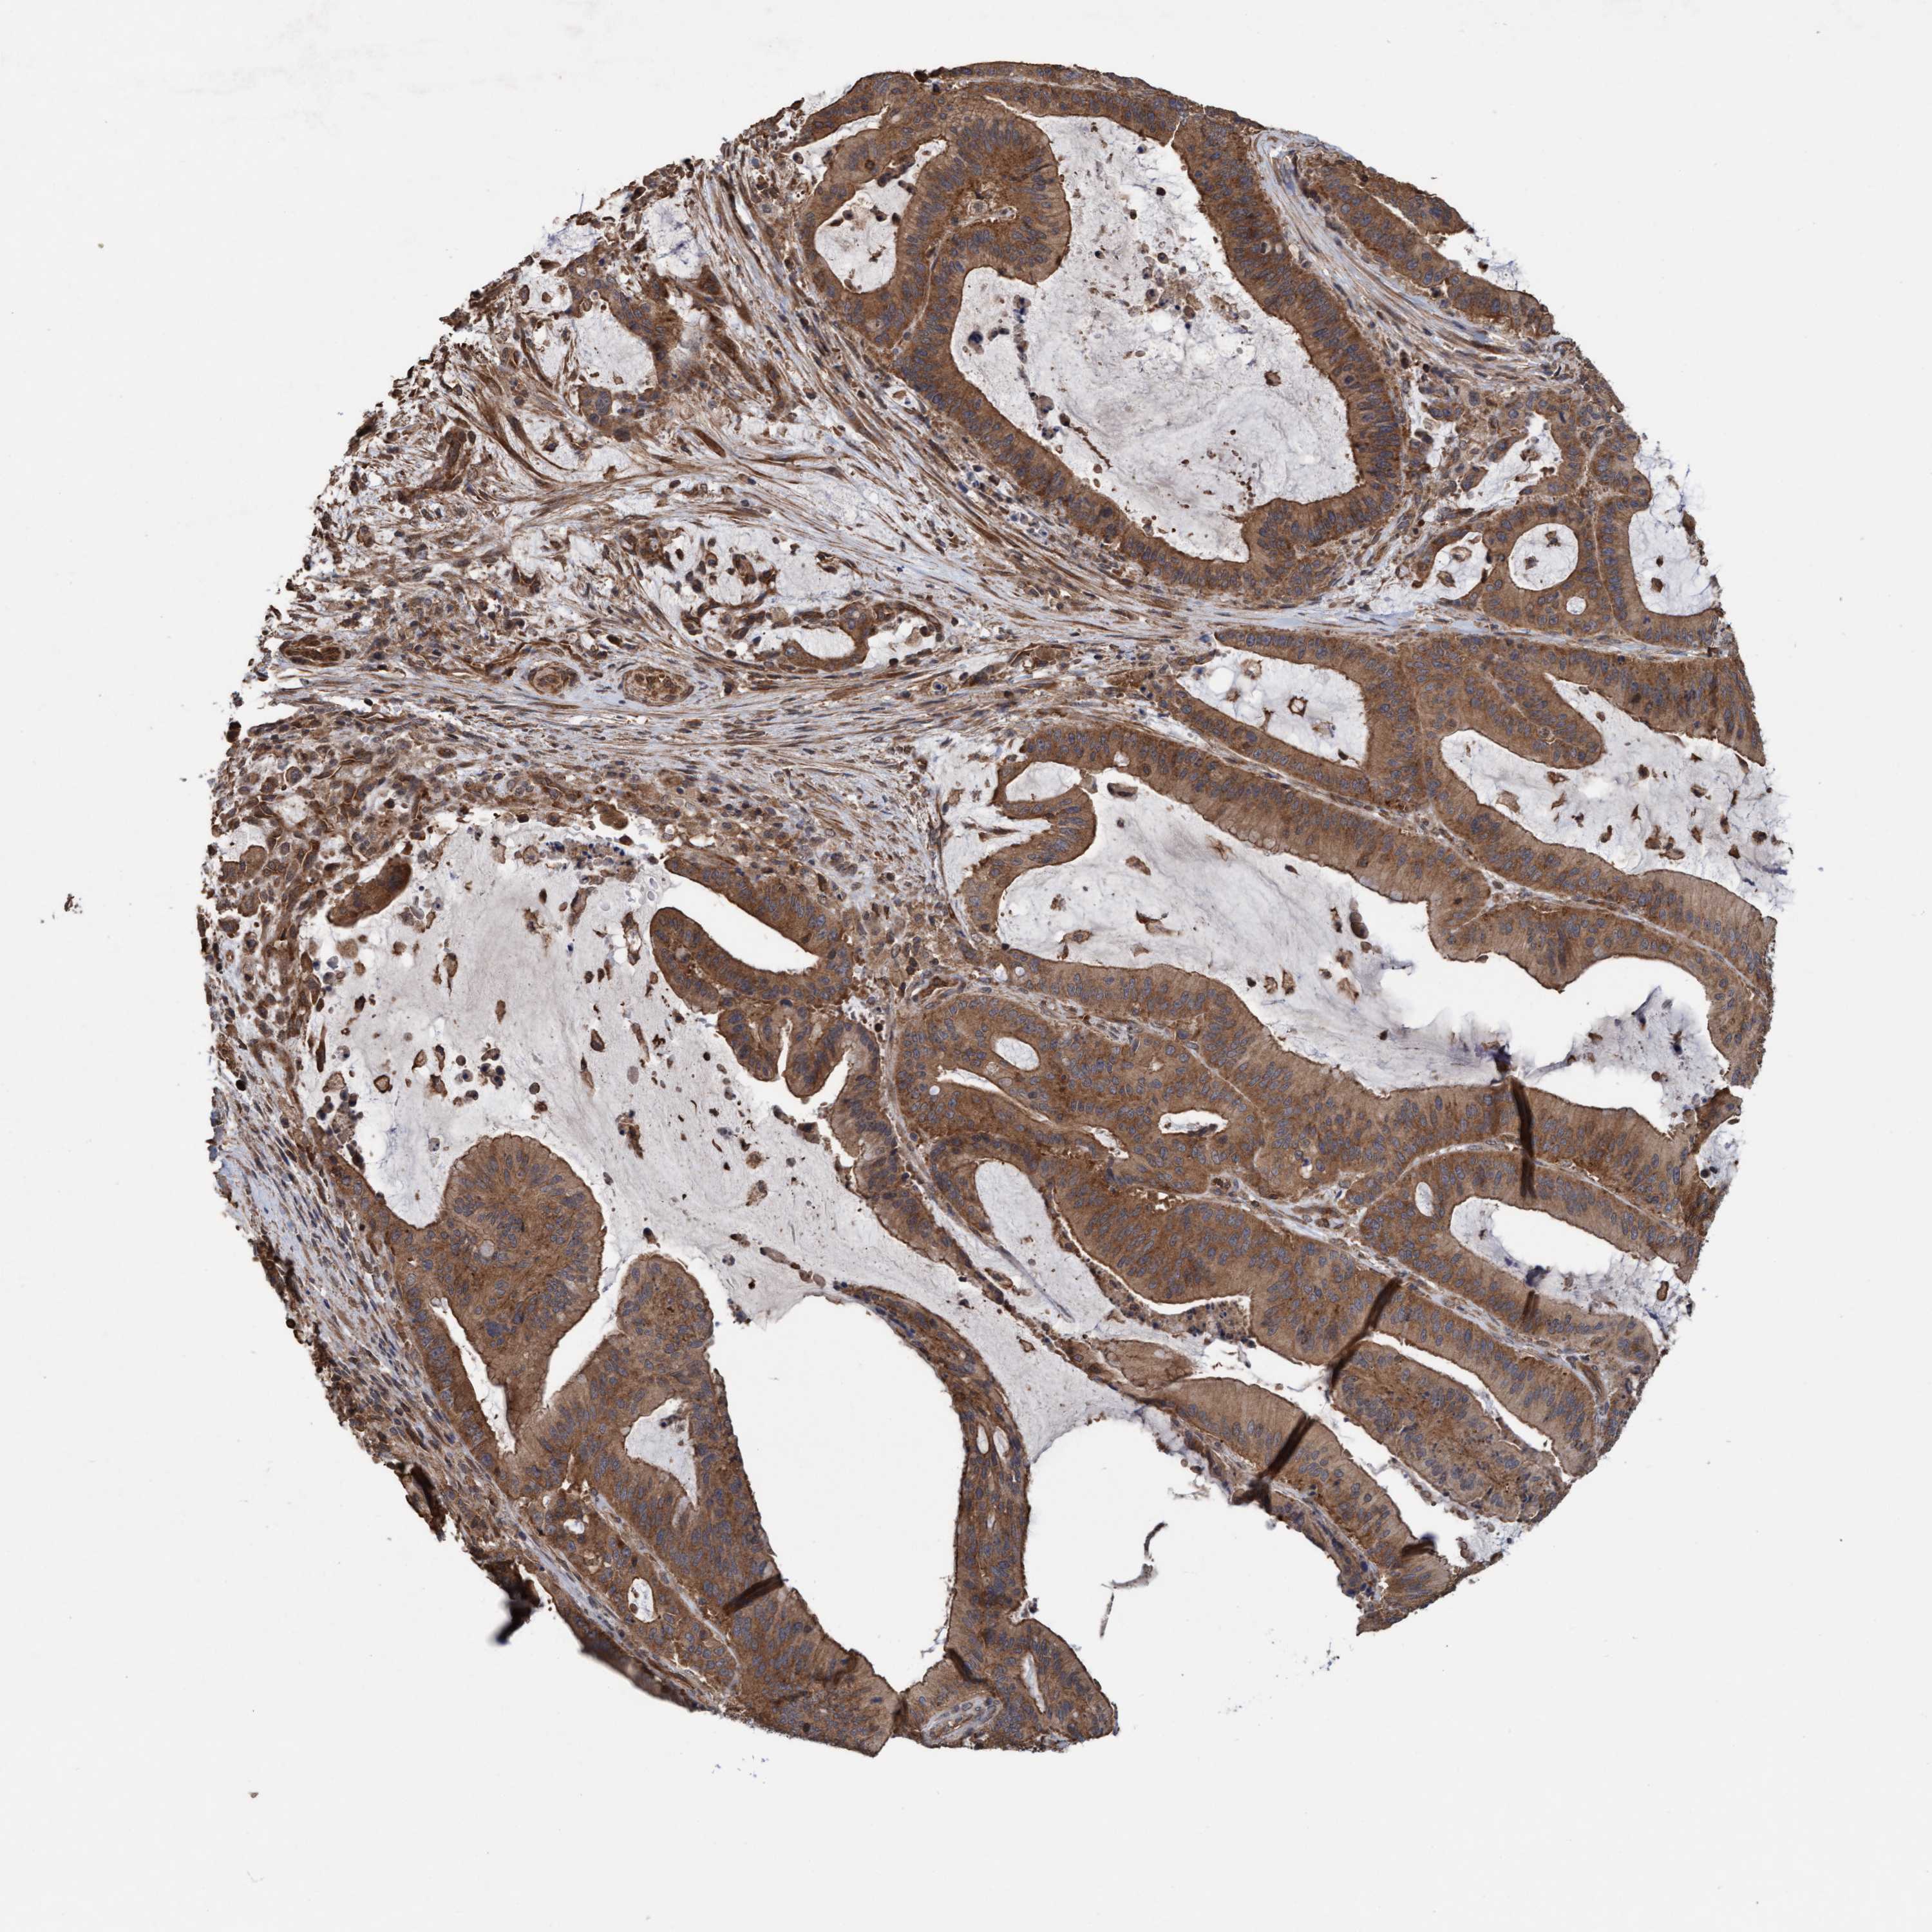

LIVER CANCER - Protein expressioni

A mouse-over function shows sample information and annotation data. Click on an image to view it in a full screen mode. Samples can be filtered based on level of antibody staining by selecting one or several of the following categories: high, medium, low and not detected. The assay and annotation is described here.

Note that samples used for immunohistochemistry by the Human Protein Atlas do not correspond to samples in the TCGA dataset.

Antibody stainingi

Antibody staining in the annotated cell types in the current human tissue is reported as not detected, low, medium, or high, based on conventional immunohistochemistry profiling in selected tissues. This score is based on the combination of the staining intensity and fraction of stained cells.

Each image is clickable and will lead to virtual microscopy that enables deeper exploration of all samples and also displays staining intensity scores, fraction scores and subcellular localization as well as patient and tissue information for each sample.

Antibody HPA022997

Antibody CAB011205

Staining

High

Medium

Low

Not detected

Intensity

Strong

Moderate

Weak

Negative

Quantity

>75%

75%-25%

<25%

None

Location

Nuclear

Cytoplasmic/membranous

Cytoplasmic/membranous,nuclear

Cholangiocarcinoma

Carcinoma, Hepatocellular, NOS